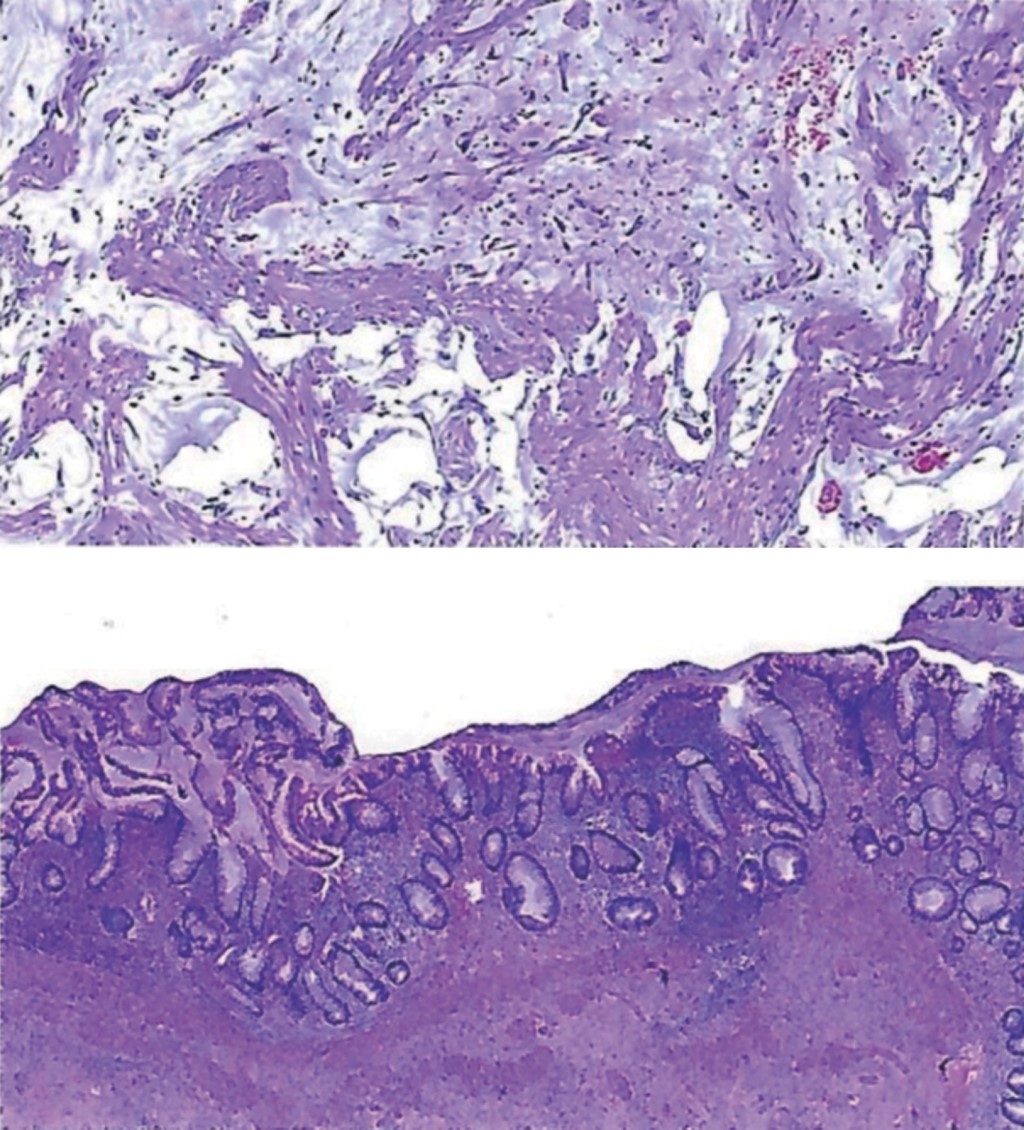

The pathology report on 06/12/22 was of a mucinous neoplasm of the ruptured cecal appendix and acute intense inflammation secondary pseudomyxoma peritoneum. The report recommended an immunohistochemical study to confirm the diagnosis and rule out malignancy (Figure 4).

Immunohistochemistry report 12/13/22: CKAE1/AE3 negative, CK20 negative, CK7 negative, MUC5 negative. The definitive diagnosis was a mucinous tumor with acute appendicitis and adenomucinosis, probable mucinous cystadenoma.

As a complement to the patient's evaluation, the tumor tissue was subjected to CK20 and CK7 immunohistochemistry. CK20 is a cytokeratin and a marker of intestinal tumors, and CK7 is a cytokeratin and a marker of gynecologic malignancies,9 reported as an adjuvant in diagnosing this entity. The immunohistochemistry result was negative.

Figure 3

Figure 4